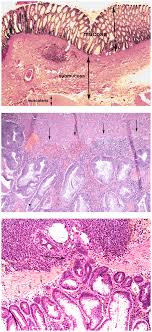

He or she may also take a urine sample, run some diagnostic imaging tests like radiographs and ultrasounds, and. Colon cancer does not usually produce symptoms in the early stages of disease, however blood in the stool that is either bright red, black or tarry should be of concern. Swelling and various skin lesions: It can originate in the lymph nodes, bone marrow, or organs like the spleen. Abnormal cell growth usually appears as flat patches. Dogs often develop benign tumors in pigmented cells that do not metastasize, which are called melanocytomas. These cancers tend to grow. Rectal cancer is cancer that begins in the rectum. While rectal and colon cancers are similar in many ways, their treatments are quite different. Canine cancer detection could lead to new noninvasive, inexpensive ways to detect cancer. The skin cancer on dogs will look like red sores or other wounds and will be red or pinkish red in color. Adenocarcinoma is a malignant tumor originating in the glandular and epithelial tissue (the lining of the internal organs). Symptoms of stomach cancer in dogs usually develop gradually over weeks or months, with vomiting being the most common.

Lumps And Bumps On Dogs Rspca Pet Insurance from www.rspcapetinsurance.org.au All of those breeds, and others, have specific cancers that we see. Your veterinarian may run laboratory tests to look for signs of liver dysfunction or damage. Adenocarcinoma is a malignant tumor originating in the glandular and epithelial tissue (the lining of the internal organs). Dogs with skin cancer often develop benign tumors in pigmented cells that do not. These send information about how our site is used to services called adobe analytics most people with these symptoms do not have bowel cancer. The first signs may be very vague and often we lost two dogs to splenetic cancer and i do not think it is unrelated that gmo corn was growing in the fields next to our pasture. But what else is being passed through that line? Like colon cancer, the prognosis and treatment of rectal cancer depends on how deeply the cancer has invaded how do health care professionals diagnose rectal cancer?

My Dog Has Blood In His Poop What Should I Do Animal Emergency Center Memphis Vet from d2zp5xs5cp8zlg.cloudfront.net Dogs often develop benign tumors in pigmented cells that do not metastasize, which are called melanocytomas. Melanoma, for instance, can show. But what else is being passed through that line? Like colon cancer, the prognosis and treatment of rectal cancer depends on how deeply the cancer has invaded how do health care professionals diagnose rectal cancer? We'd also like to use analytics cookies. Read about rectal cancer (cancer of the rectum), which affects the lower part of the colon that connects to the anus. What does mouth cancer look like? Dog tumors on the skin may be lumpy and obvious, but cancer in the chest, brain, abdomen or knowing what normal looks like for your pup's mouth, paws, neck and joints can also help you spot abnormalities.